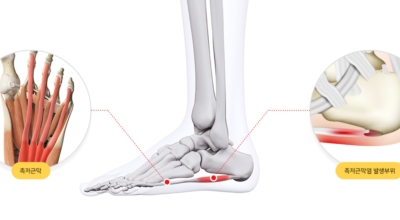

족저 근막이란 발가락 시작지점부터 발뒤꿈치뼈까지 발바닥 전체를 감싸고 있는 두꺼운 막을 말해요. 족저 근막은 발바닥 아치를 지속시켜 발바닥이 지면을 내딛음으로써 나타나는 충격을 흡수하는 중요한 역할을 수행하고 있어요. 이 족저 근막에 일차적으로 서서히 조직 손상이 일어나고 계속적인 활동으로 인해 염증이 커지면서 발 뒤꿈치 부근 통증을 유발하게 되는데 염증은 무리하고 반복적인 동작, 과도한 사용으로 마찰에 의해 발생해요.

족저근막염은 여러가지 원인으로 발생할 수 있기 때문에 정확한 원인을 파악하고 적절한 치료를 받는 것이 중요해요. 구조적으로 평평한 발을 가지거나 정상보다 높은 아치를 가진 사람들은 족저근막염이 발병할 가능성이 더 큽니다. 다리 길이의 차이나 발 형태의 해부학적 이상도 족저근막염에 걸리기 쉽습니다.